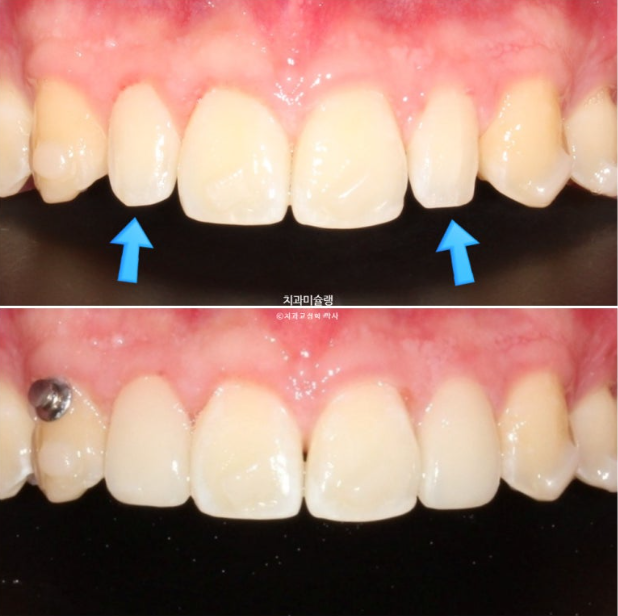

파란 화살표가 가위교합이고 위 큰어금니는 바깥으로 나가있고 대합치는 안쪽으로 쓰러지며 가위처럼 서로 엇갈려 교합되는 상태를 말합니다.

파란 화살표 치아가 바깥으로 뻗치면서 가위교합의 원인이 됩니다.